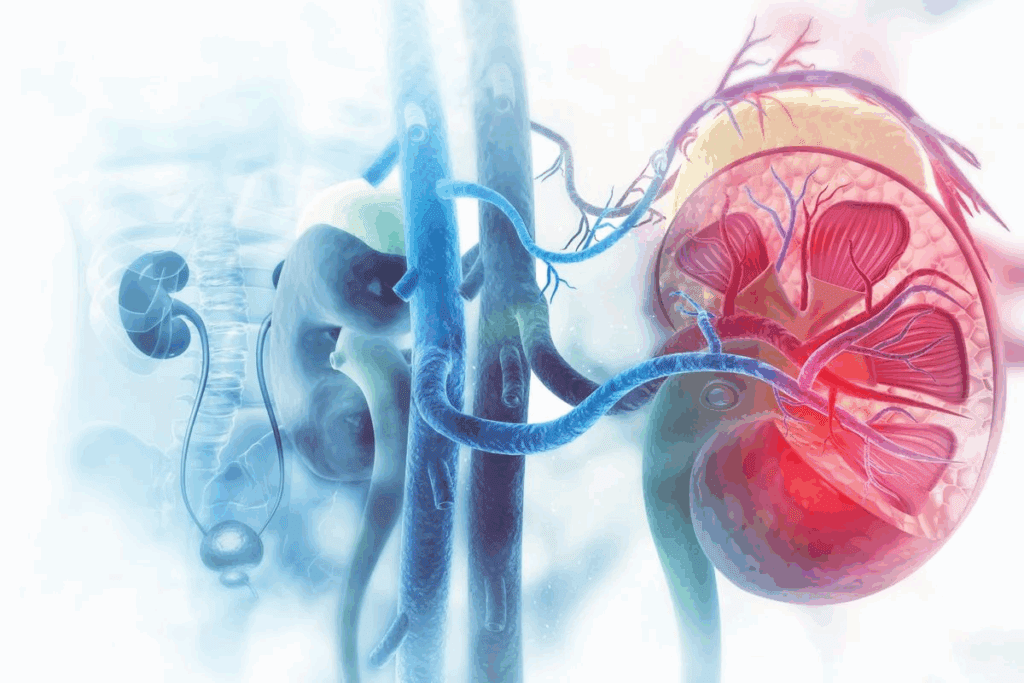

Understanding Kidney Tumors and Renal Cell Carcinoma

It’s important to know about kidney tumors to plan the best treatment. Most kidney cancers are renal cell carcinoma. These tumors can be harmless or cancerous.

Types and Stages of Kidney Tumors

Kidney tumors are divided by their type and how they grow. Renal cell carcinoma starts in the kidney’s lining. It’s the most common kidney cancer in adults.

The cancer’s stage is key for treatment. For small tumors, surgery is often the best choice. This helps keep the kidney working well.